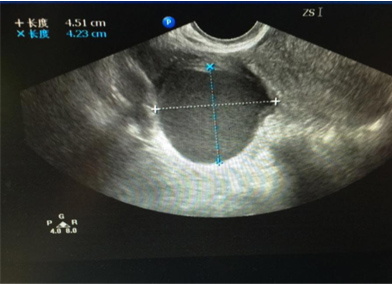

王女士,今年36岁,单位体检发现一侧卵巢有一直径约4cm大小的囊肿,没有什么不舒服,一听说有卵巢囊肿,王女士很紧张的来到我们妇科门诊就诊,问:“医生,我现在该怎么办?我这

个囊肿会不会是癌症?需不需要马上就手术?……”

大部分卵巢囊肿都是卵巢排卵后卵巢修复过程中形成的,多随卵巢周期性变化而产生和消失,因此常见于生育年龄的女性。对于卵巢排卵,多数卵巢外观不会出现明显的变化,只有少数情况形成囊肿,一般形成的囊肿也不会太大,一般是一侧卵巢可见囊肿,我们临床医生称之为“生理性囊肿”,并且多数以5cm为界限,也有以8cm为界限。也就是说5cm之内的“生理性囊肿”,我们不需要采取任何措施,囊肿多数会自然消退,持续的时间长短因个人而异,有持续1个月或数月不等,通常会在三个月内自行消失。而对于超过5cm的囊肿,或持续存在,或变大,可能是病理性囊肿,比如卵巢囊性畸胎瘤、各种囊腺瘤,甚至少数是囊腺癌,因此这种情况下,我们建议手术治疗。